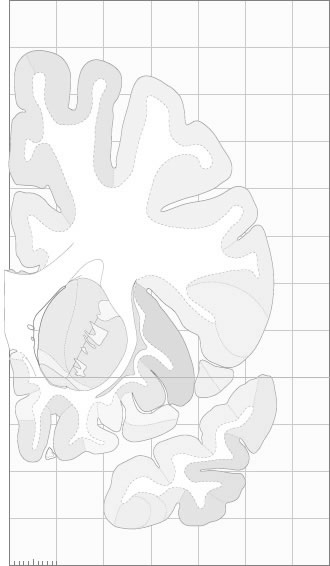

Hi-Resolution Sections · Cells (Nissl Staining) · Virtual Microscopy

Frontal sections (Nissl) from the Atlas Brain:

Schematic

Slice ID:

r2-0670

Plate NR:

09-10

Position:

-21,6 mm